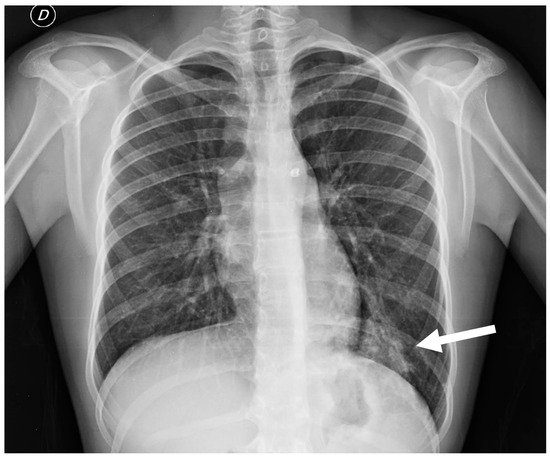

3.6.1. Pulmonary Sequestration